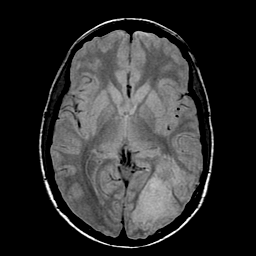

Sarcoma, MR Study #1 mr-pd -- Slice #11

[Home][Help][Clinical] Slice 11